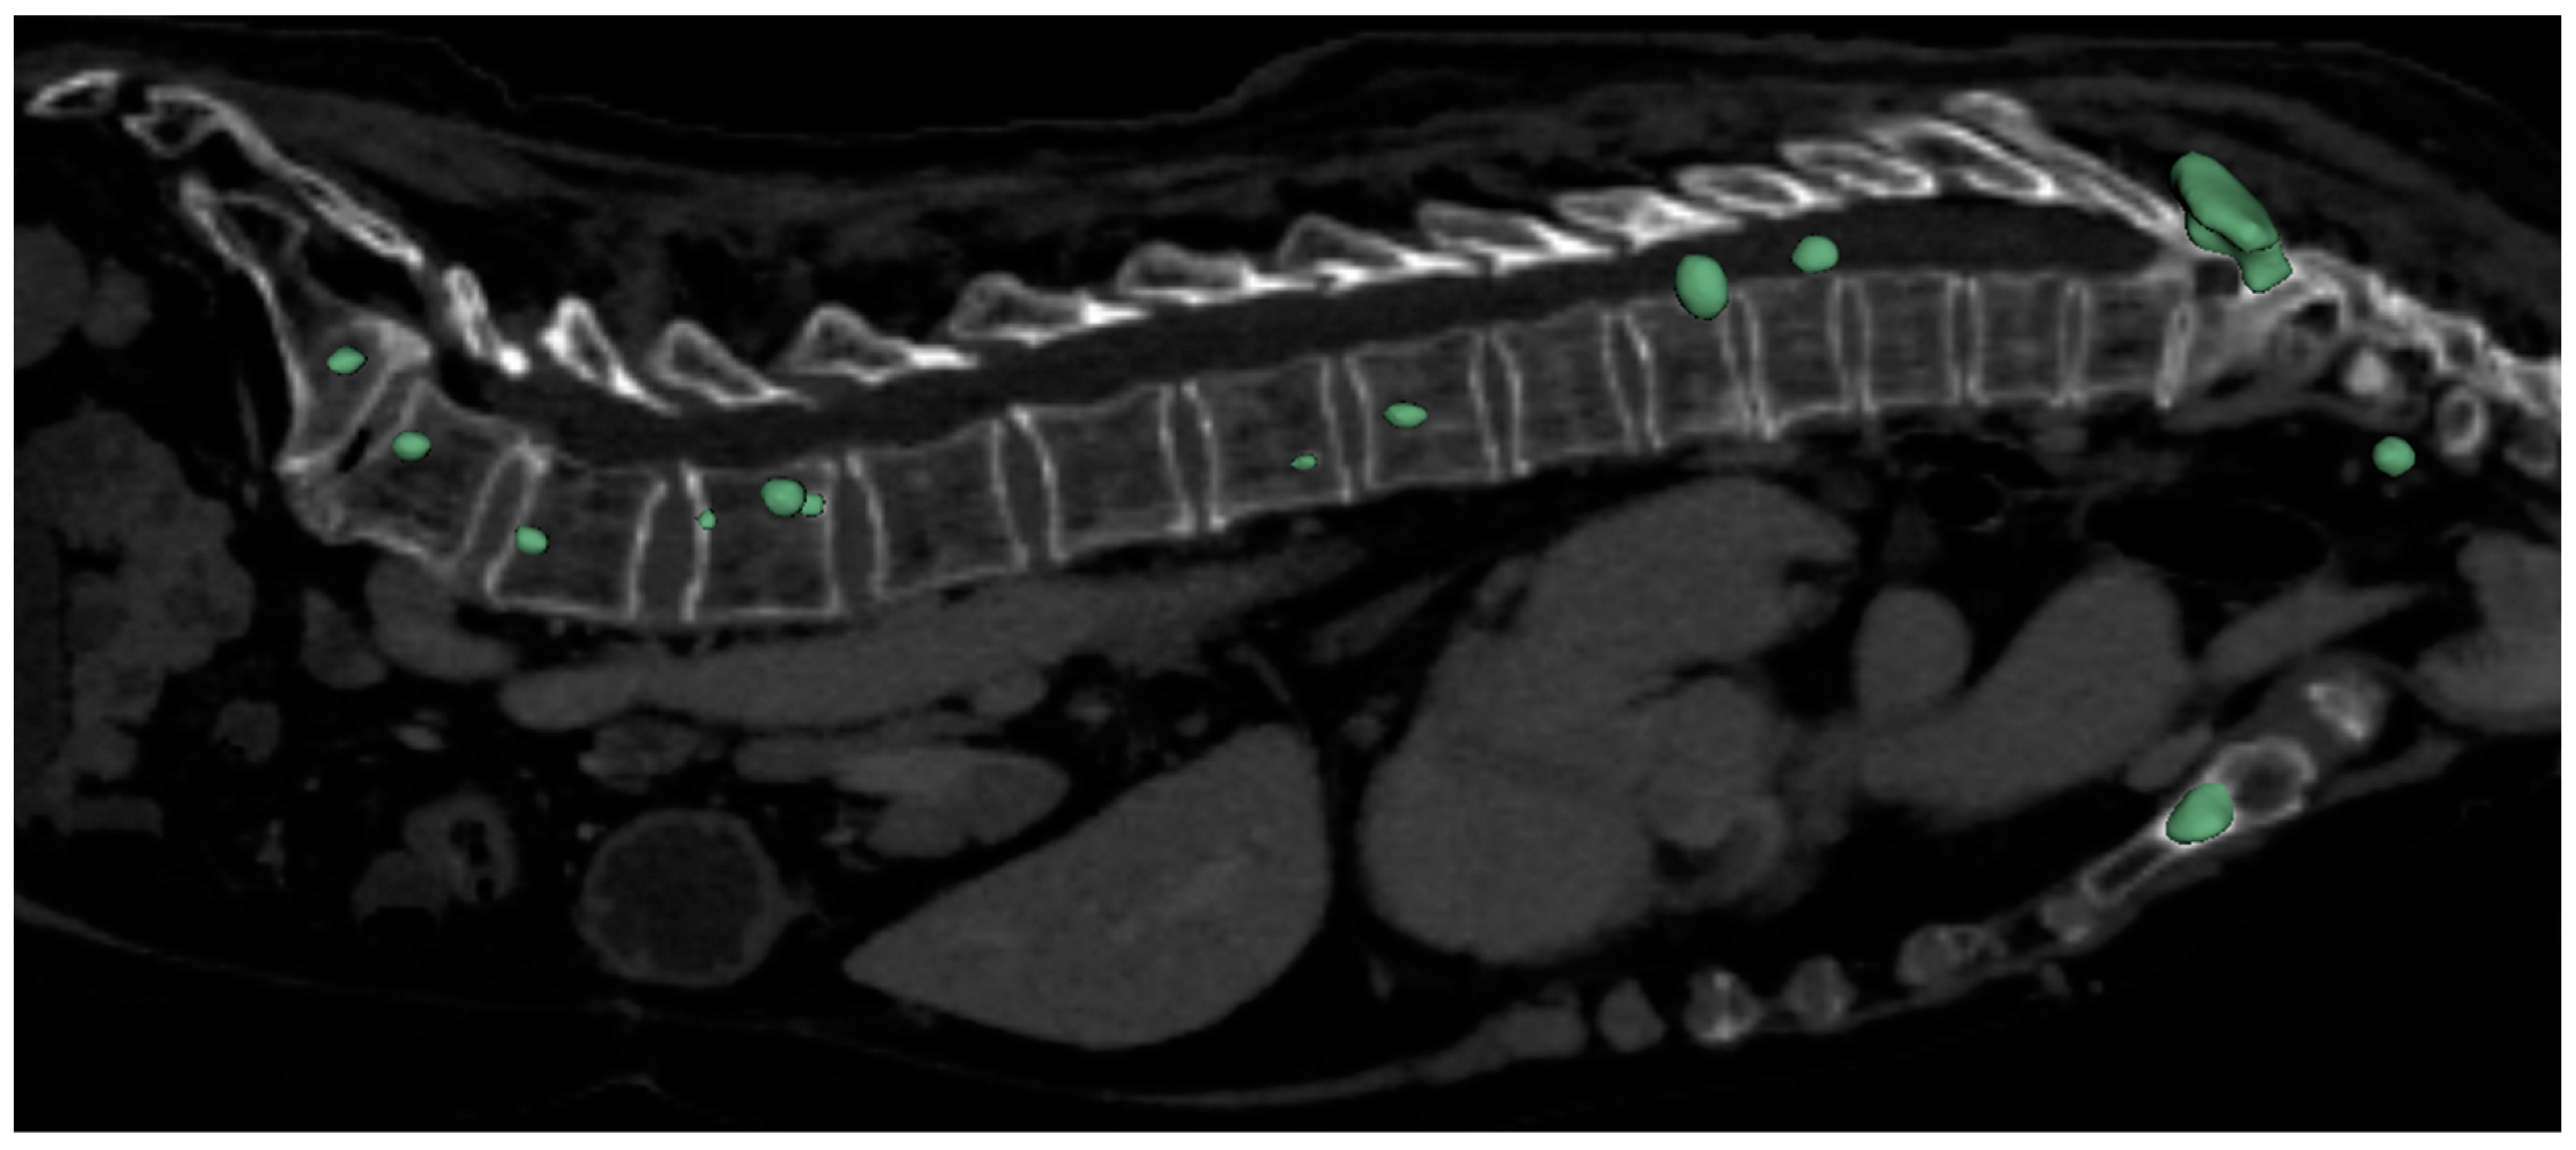

- Edelmers, E.; Kazoka, D.; Bolocko, K.; Sudars, K.; Pilmane, M. Automatization of CT Annotation: Combining AI Efficiency with Expert Precision. Diagnostics 2024, 14, 185. [Google Scholar] [CrossRef] [PubMed]

- Edelmers, E. CT Scans of Spine with Metastases (Lytic, Sclerotic). 2024. [Google Scholar] [CrossRef]